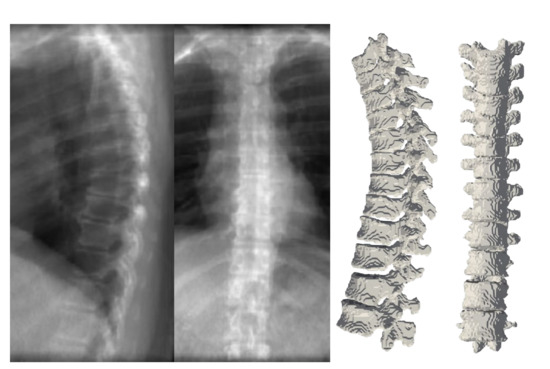

We employ a ray-casting approach [36] to construct DRRs from CT scan. In this method, we define lines from the radiation source (focal point) to every single pixel on the DRR image and calculate the integral of the CT intensities over these lines. In this simulation we assign ( 180 cm ) and ( 150 cm ) to the radiation source-to-detector distance and the source-to-object distance parameters respectively. Examples of patches extracted from DRRs are illustrated in Figure 6 and Figure 7. Also, a complete example of orthogonal DRRs is shown in Figure 8.

Figure 6 depicts coronal and sagittal image patches from three vertebrae, mid-slice of the resulting estimated displacement field and vertebral shape. In the estimated displacement field the brighter colors indicate greater displacements. Figure 7 shows an example point cloud (with 2048 points) from the predicted and ground truth shapes, along with a point-wise Chamfer distance map. Observe that the vertebra’s posterior region (vertebral process) is hardly visible in the image inputs. In spite of this, TransVert+ was able to reconstruct the 3D shape of vertebral processes. To calculate the Chamfer distance map for each point in the reconstructed vertebra’s point cloud, the nearest point in the ground truth point cloud is found and the square of distance is depicted. Figure 8 illustrates a 3D spine reconstruction based on 2D DRRs.

Figure 8. Orthogonal DRRs of a patient and reconstructed 3D spine model. DRRs are generated from CT scans and our model is trained to reconstruct the 3D spine shape from DRRs.